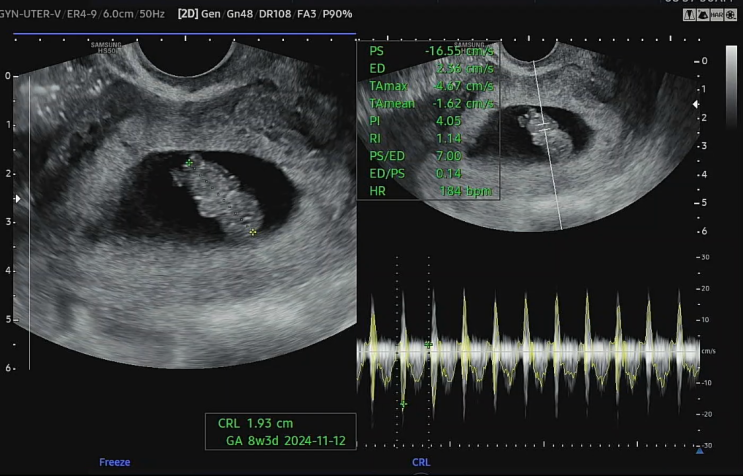

난임일기 동결1차 #7 - 5일배양포배기 이식 19일차. 입터짐, 아기집확인, 난황확인, 파이널임테기, 스마일더블체크.

3/8 19일차 5주2일 아기집.난황확인 드디어 아기집 보러가는 날 사실 1차,2차 피검때 보다 더 가슴 졸였던 ...